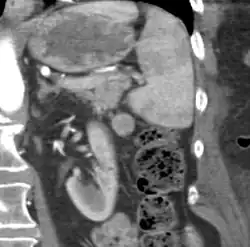

If splenectomy is performed for conditions in which blood cells are sequestered in the spleen, failure to remove accessory spleens may result in the failure of the condition to resolve.[1] During medical imaging, accessory spleens may be confused for enlarged lymph nodes or neoplastic growth in the tail of the pancreas,[5] gastrointestinal tract, adrenal glands or gonads.[2]